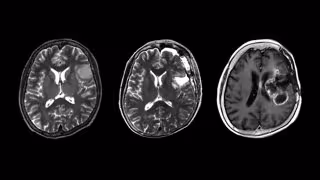

Investigadores alertan sobre el pronostico "peor de lo esperado" de un tipo raro de astrocitoma

Astrocitoma, tumor neuronal tipo raro

Un equipo de investigadores de la Facultad de Medicina de la Universidad de Nagoya (Japón) ha informado que los pacientes con una forma rara de cáncer de cerebro y de médula espinal, el astrocitoma histológicamente difuso de isocitrato deshidrogenasa de tipo salvaje (IDHwt) localizado, tienen un mal pronóstico, similar al de los tipos más malignos de tumores cerebrales y de médula espinal.

El equipo de investigación de la Universidad de Nagoya, dirigido por Yuji Kibe y Kazuya Motomura del Departamento de Neurocirugía, analizó los astrocitomas IDHwt localizados y descubrió que todos resultaron en una recurrencia maligna y un pronóstico clínico precario similar al de los glioblastomas. Los glioblastomas se encuentran entre los tumores más malignos, con un tiempo de supervivencia promedio de 8 meses y menos del 7 por ciento de los pacientes sobreviven cinco años.